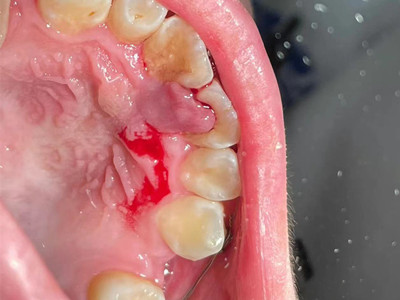

牙龈癌多源于牙间乳头及龈缘区,溃疡呈表浅、淡红,以后可出现增生。由于黏骨膜与牙槽突附着甚紧,较易早期侵犯牙槽突骨膜及骨质,进而出现牙松动,并可发生脱落。X线片可出现恶性肿瘤的破坏特征虫蚀状不规则吸收。

牙龈癌常发生继发感染,肿瘤伴以坏死组织,触之易出血。体积过大时可出现面部肿胀,浸润皮肤。